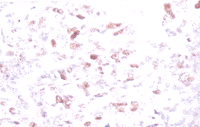

PCNA阳性镜下表现为细胞核染色,呈棕褐色颗粒状,胞浆不着色(见图1、图2)。

图1 卵巢粘液性腺癌(低分化)PCNA蛋白阳性(+++)×20

图2 卵巢浆液性腺癌(低分化)PCNA蛋白阳性(++++)×20